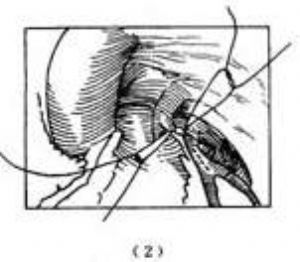

(3)肺動脈內通道術:這種手術進入臨牀應用僅有十多年的歷史,其優點是無需解剖遊離左冠狀動脈和對細小的冠狀動脈施行操作難度較大的切開縫合術,特別適用於左冠狀動脈開口位於肺動脈左側壁,因而長度較短的病例。

胸骨正中切口,切開心包,建立體外循環結合中等度低溫或深低溫。在靠近肺動脈瓣上方切開肺動脈左側壁,顯露左冠狀動脈開口部位,然後在升主動脈左壁與肺動脈緊鄰部位各切除徑約5~6mm的環狀主動脈和肺動脈壁,直接縫合主動脈壁與肺動脈壁的小窗形成人造的主-肺動脈瘻。在主-肺動脈瘻的上方另作肺動脈橫向切口,到達肺動脈左壁時,再向下切開與肺動脈壁下方橫切口相聯接,這樣在肺動脈前壁形成平行的長方形血管壁瓣片,將此瓣片縫合於肺動脈後壁,瓣片的右端和左端分別縫合於主-肺動脈瘻和左冠狀動脈開口的四周,於是血液即可從升主動脈通過主-肺動脈瘻再經肺動脈腔內由肺動脈前壁縫成的通道進入左冠狀動脈。肺動脈前壁遺留的缺損區則用心包片或絛綸織片覆蓋縫補,肺動脈腔內血流通道亦可用心包片(Hamilton,1979)或遊離的一段自體鎖骨下動脈(arciniegas,1980)替代肺動脈前壁(圖3)。影響手術死亡率的主要因素是病情輕重程度和手術時病人的年齡。術前心功能在Ⅲ級以下者,手術死亡率低於20%,術前心功能Ⅳ級或病情危重需緊急手術者則手術死亡率高達70%。arciniegas報道一組19例病人,手術時年齡在1歲以內的12例中,2例死亡;而1~2歲的7例無一死亡。由於左冠狀動脈異位起源於肺動脈的病例不多見,開展外科治療爲期尚短,遠期隨訪觀察的病例數不多。Kirklin和Barratt-Boyes對此術後生存的19例病人,隨訪時間最長的19年,僅1例死亡,17例術後心功能爲I級,另1例爲Ⅱ級。左室顯著縮小,心肌缺血的症狀和徵象明顯減輕。由於心肌缺血引致中等度二尖瓣關閉不全者,大多數病例術後仍可聽到心尖區收縮期雜音。

圖3 肺動脈內通道術

⑴肺動脈切口;⑵主動脈-肺動脈吻合;⑶肺動脈前壁瓣片與肺動脈後壁縫合形成通道;⑷用心包片縫補肺動脈前壁缺損